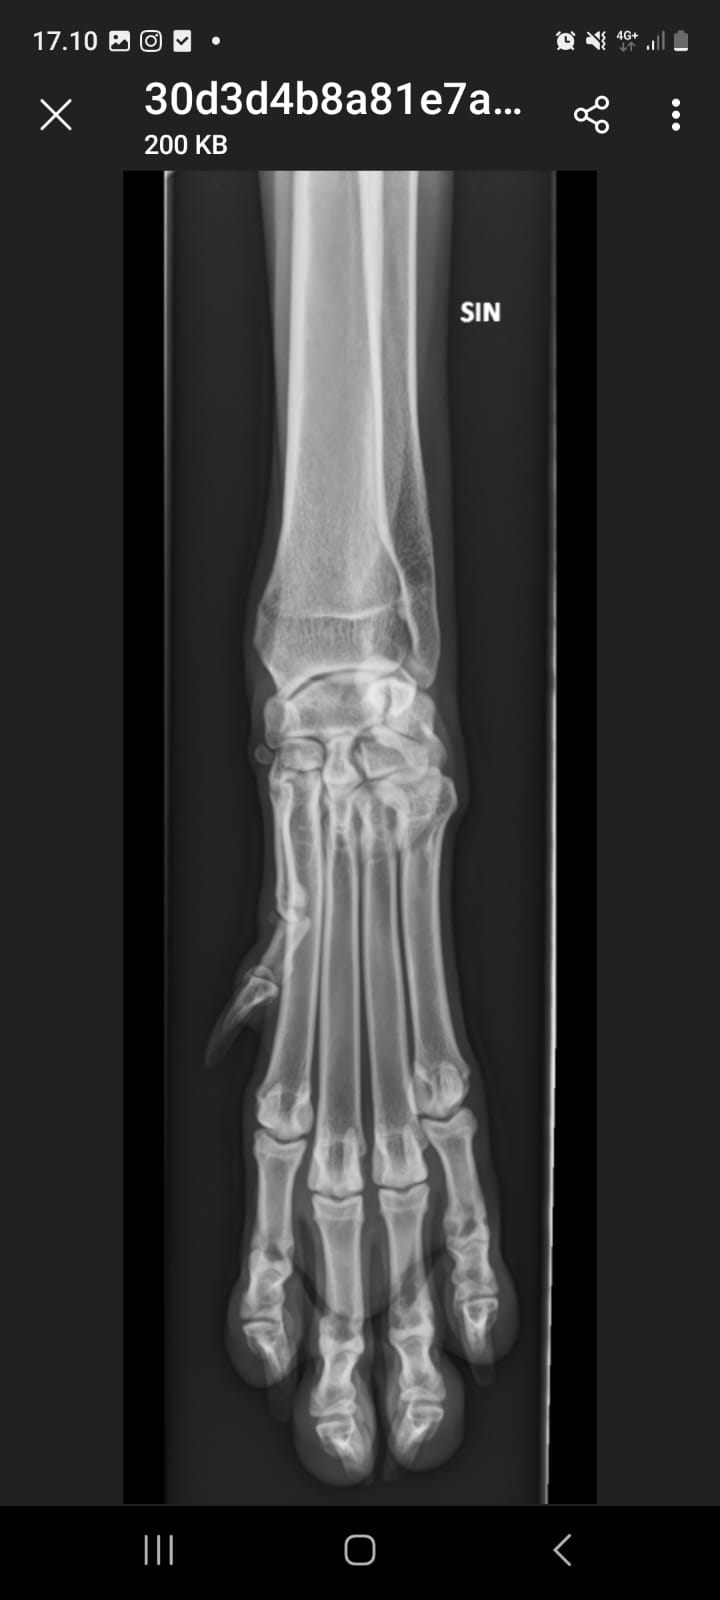

- Kasvuajan luustosairaus (HOD) ilmenee verenvuotona ja kalkkeutumina aivan luukalvojen alla, varsinkin ranteiden yläpuolella. Ulospäin sairaus näkyy lämpimänä turvotuksena kyynärluiden ja värttinäluiden alaosassa eli ranteiden yläpuolella. Koira aristaa usein jalkojaan, ontuu, pahimmassa tapauksessa koira ei pysty edes seisomaan. Sairauteen liittyy useasti kuume ja yleiskunnon heikkeneminen. Tämä sairaus on tyypillinen nimenomaan suurille, nopeakasvuisille roduille, yleinen esiintymisikä 3-6 kk. Muutokset näkyvät röntgenkuvissa selvästi.

- Voimalla HOD oireili ranteissa. Ranteet kuvattiin ja sieltä tyypillinen tulehduksellinen löytö. Hoitona oli kipulääke-kuuri sekä antibiootti. HOD ei ole perinnöllinen. Näin kriittisessä kasvuvaiheessa oleva HOD on voinut kuitenkin vaurioittaa tulehtuneen nivelen nivelpintaa ja näin ollen aiheuttaa kasvuhäiriön.

- ranteet kuvattu terveiksi 08/25!